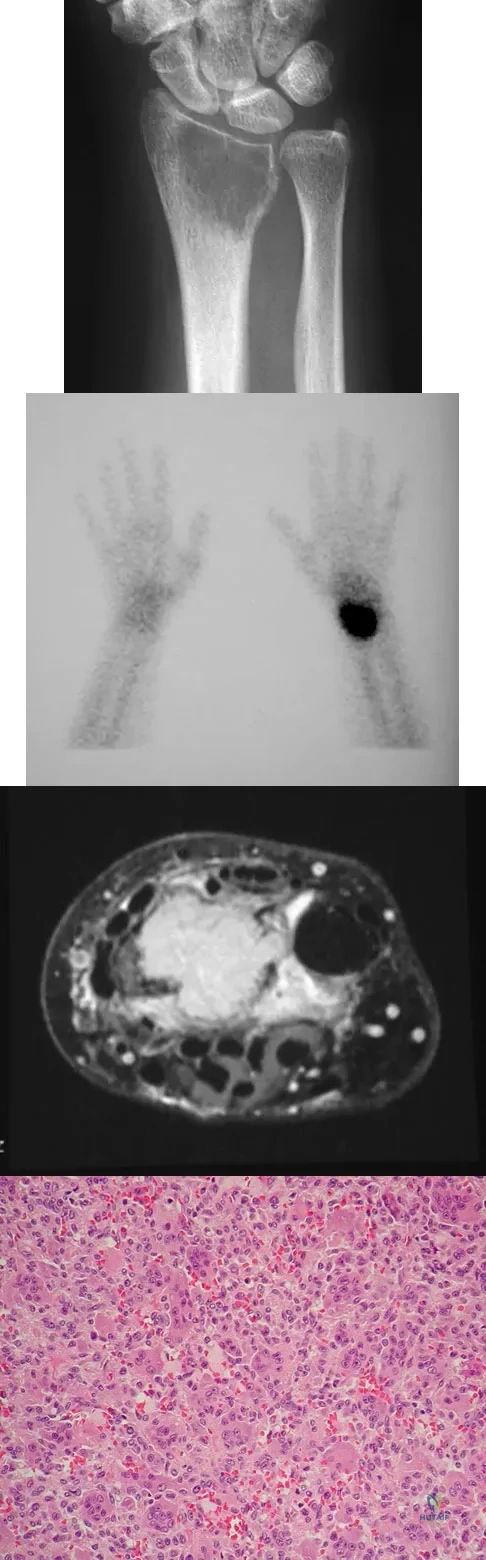

Question 6

A 45-year-old woman has had right wrist pain for the past 2 months. A radiograph, bone scan, and MRI scan are shown in Figures 66a through 66c, and a photomicrograph is shown in Figure 66d. What is the most likely diagnosis?

Explanation